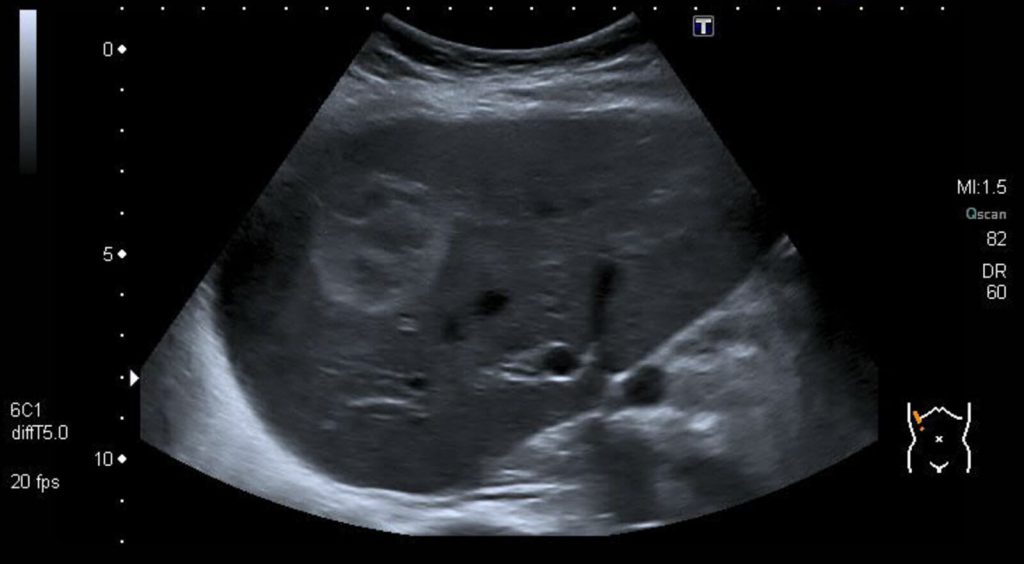

کارسینوم هپاتوسلولار (HCC)

کارسینوم هپاتوسلولار (HepatoCellular Carcinoma=HCC) تومور بدخیم کبد است که معمولاً مفرد و تنها (solitary) میباشد. این بدخیمی به صورت اولیه در بیماران با سیروز کبدی و هپاتیت مزمن به وجود میآید. اساساً این بیماری، یک تشخیص تصادفی است که از طریق سونوگرافی یا سطح بالای آلفا فتو پروتئین (a-fetoprotein) تشخیص داده میشود.